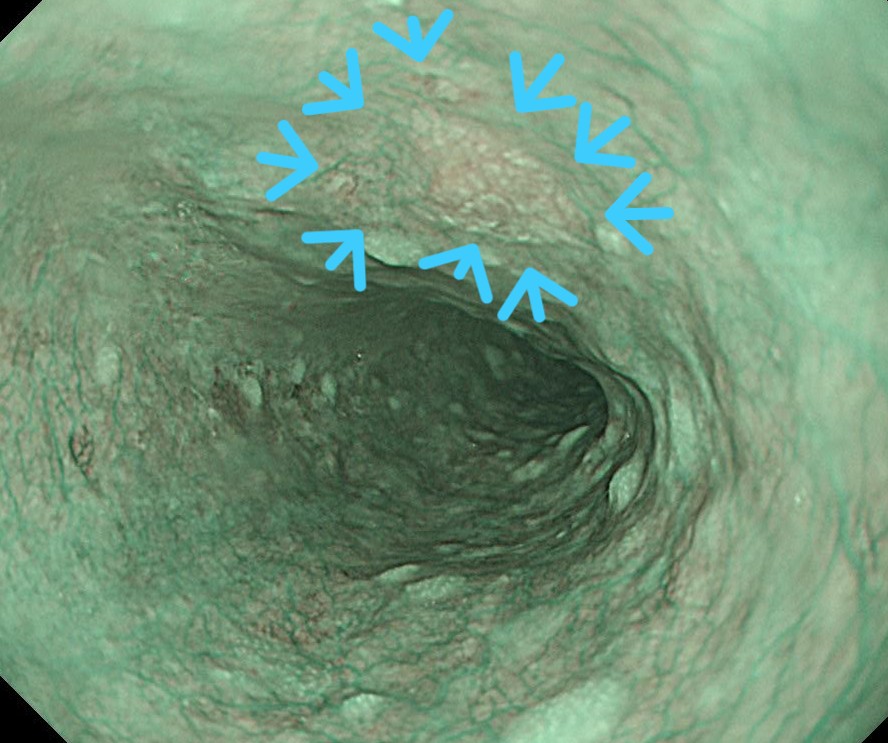

胸部中部食道にNBIで明瞭なブラウンlesionとなる病変が認められます。